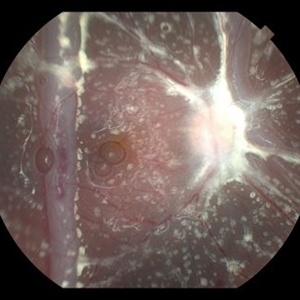

Giant Retinal Tear with Choroidal Detachment

Giant Retinal Tear with Choroidal Detachment

Jun 12 2024 by Anand Temkar

Intra operative still of a 34 year old male showing Giant Retinal Tear with Choroidal Detachment.

Photographer: Dr.Anand Temkar- Retina Foundation, Ahmedabad

Condition/keywords: choroidal detachment, giant retinal tear